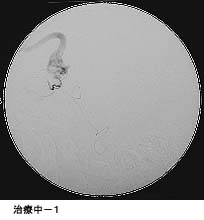

(1)破裂脳動脈瘤に対するGDC(コイル)塞栓術

*術後 コイルにより動脈瘤が写らなくなりました。